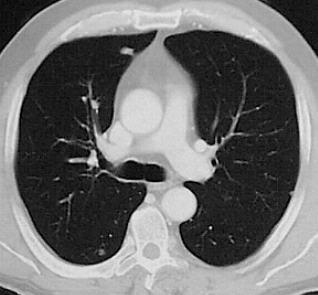

Pneumonien:

Die Lobärpneumonie, die meist durch Pneumokokken hervorgerufen wird, zeichnet sich durch eine homogene alveoläre Infiltration von Segmenten des betroffenen Lappens aus.

Dagegen ist die Bronchopneumonie (Lobulärpneumonie) durch eine multilokulär über die Lunge verstreute Infiltration der sekundären Lobuli gekennzeichnet, die sich an Lungensegmenten orientieren kann und ein Mischbild von belüfteten und nicht belüfteten Lungenarealen hervorruft.

Die interstitiellen Pneumonien werden vorwiegend von Viren, Mykoplasmen und Rickettsien hervorgerufen und sind durch feinfleckige interstitielle Infiltrationen mit verdickten Lobär- und Interlobärsepten gekennzeichnet.

Eine pulmonale Metastasierung ist häufig insbesondere bei Colon-, Pankreas-, Mamma-, Nierenzell-, Prostatakarzinomen und dem malignen Melanom. Lungenmetastasen stellen sich in der Computertomographie als meist multiple, weichteildichte Rundherde dar, die ab einer Grösse von ca. 2 mm computertomographisch nachweisbar sind. Sie treten hydrostatisch bedingt dorsobasal häufiger auf.